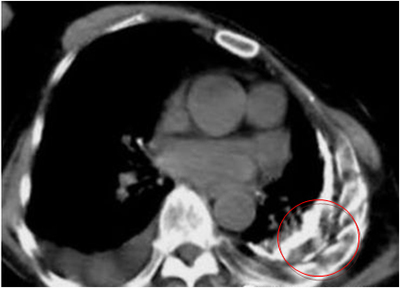

右侧胸膜增厚,左侧胸膜增厚钙化,左侧胸腔塌陷,心脏血管左移,肺功能受损

在系统抗结核治疗基础上配合胸腔穿刺抽取胸腔积液是目前治疗结核性胸膜炎的常规治疗方法,但是部分患者胸腔积液吸收不良出现胸膜增厚、胸膜粘连、肺组织局部膨胀不全,从而导致肺功能受损、并且可伴有不同程度的胸痛,影响患者的预后生活质量和身体素质,尤其是对于青、中年这一主要的劳动力群体。据报道在所有结核性胸膜炎患者中,有20%-50%可发生2-10mm的残余胸膜增厚,并且在发病后5-7天即可形成,临床预后不良率可达15.2%,严重者可致胸廓变形塌陷、肺不张。